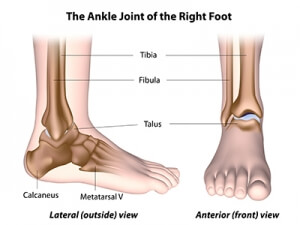

Foot & Ankle Joint Preservation

The foot and ankle form an intricate system comprising 31 bones, 33 joints, and over a hundred muscles, tendons, and ligaments. These remarkable structures serve as the foundation of our mobility, offering support, balance, and shock absorption during activities like standing, walking, and running. Their intricate design ensures our ability to move with grace and stability.